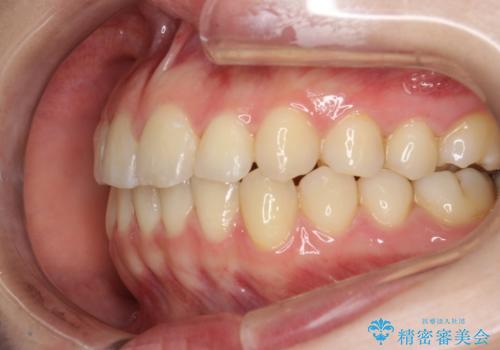

インビザラインによるガタつきの矯正治療 シンプル・短期間

- 20代女性

- invisalign full

- 1年6ヶ月

- 非抜歯、IPR+拡大によるマウスピース矯正を計画した。

一見前歯のガタつきだけのように見えても、そのガタつきの根本的な原因が奥歯の位置であったりすると、マウスピースの枚数がそれなりに多くなり、治療に時間がかかることもあります。